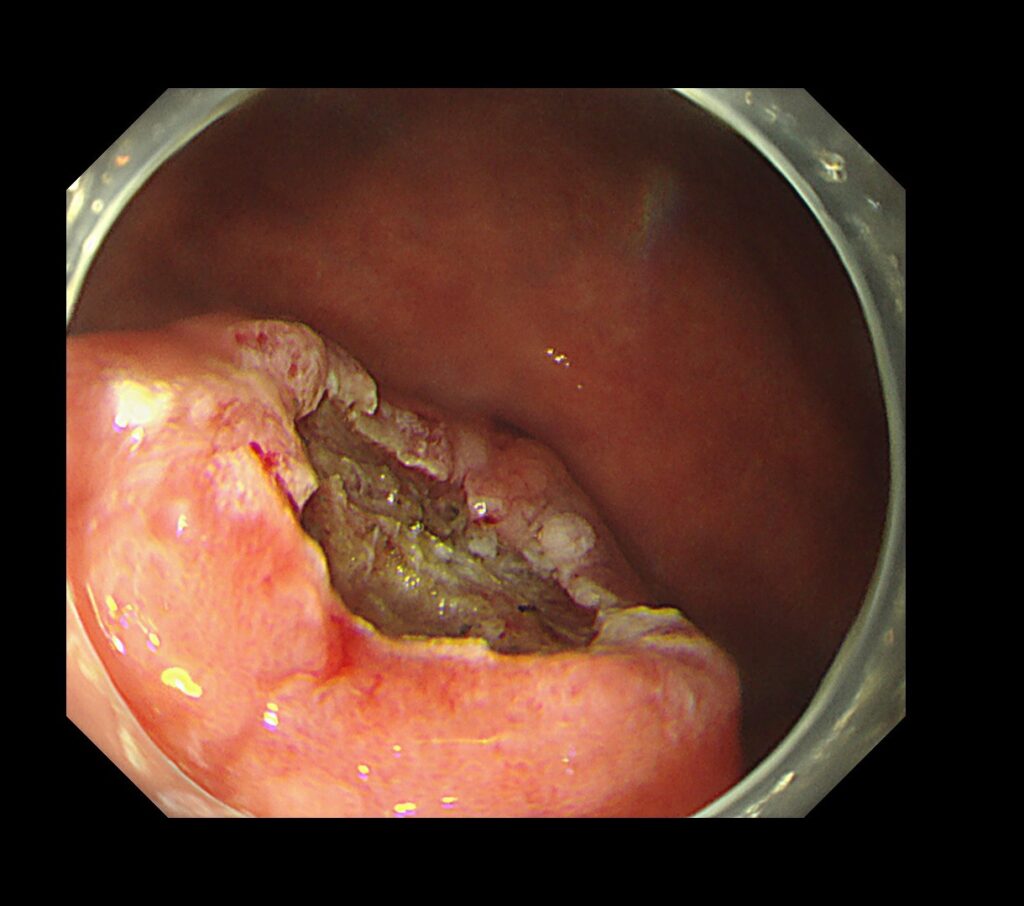

胃の下部の病変です。通常観察では、局在診断が困難な症例です。

拡大観察すると、やや凹んだ部位(陥凹部)に一致して、領域(境界明瞭)のある癌がわかるかと思います。